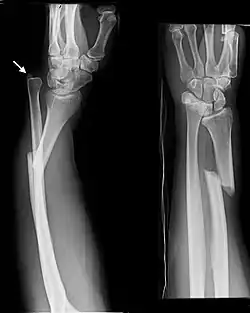

- Monteggia fracture - a fracture of the near to elbow end of the ulna with the dislocation of the head of the radius at the elbow joint.[2]

Monteggia Fracture (fracture of proximal ulna) -